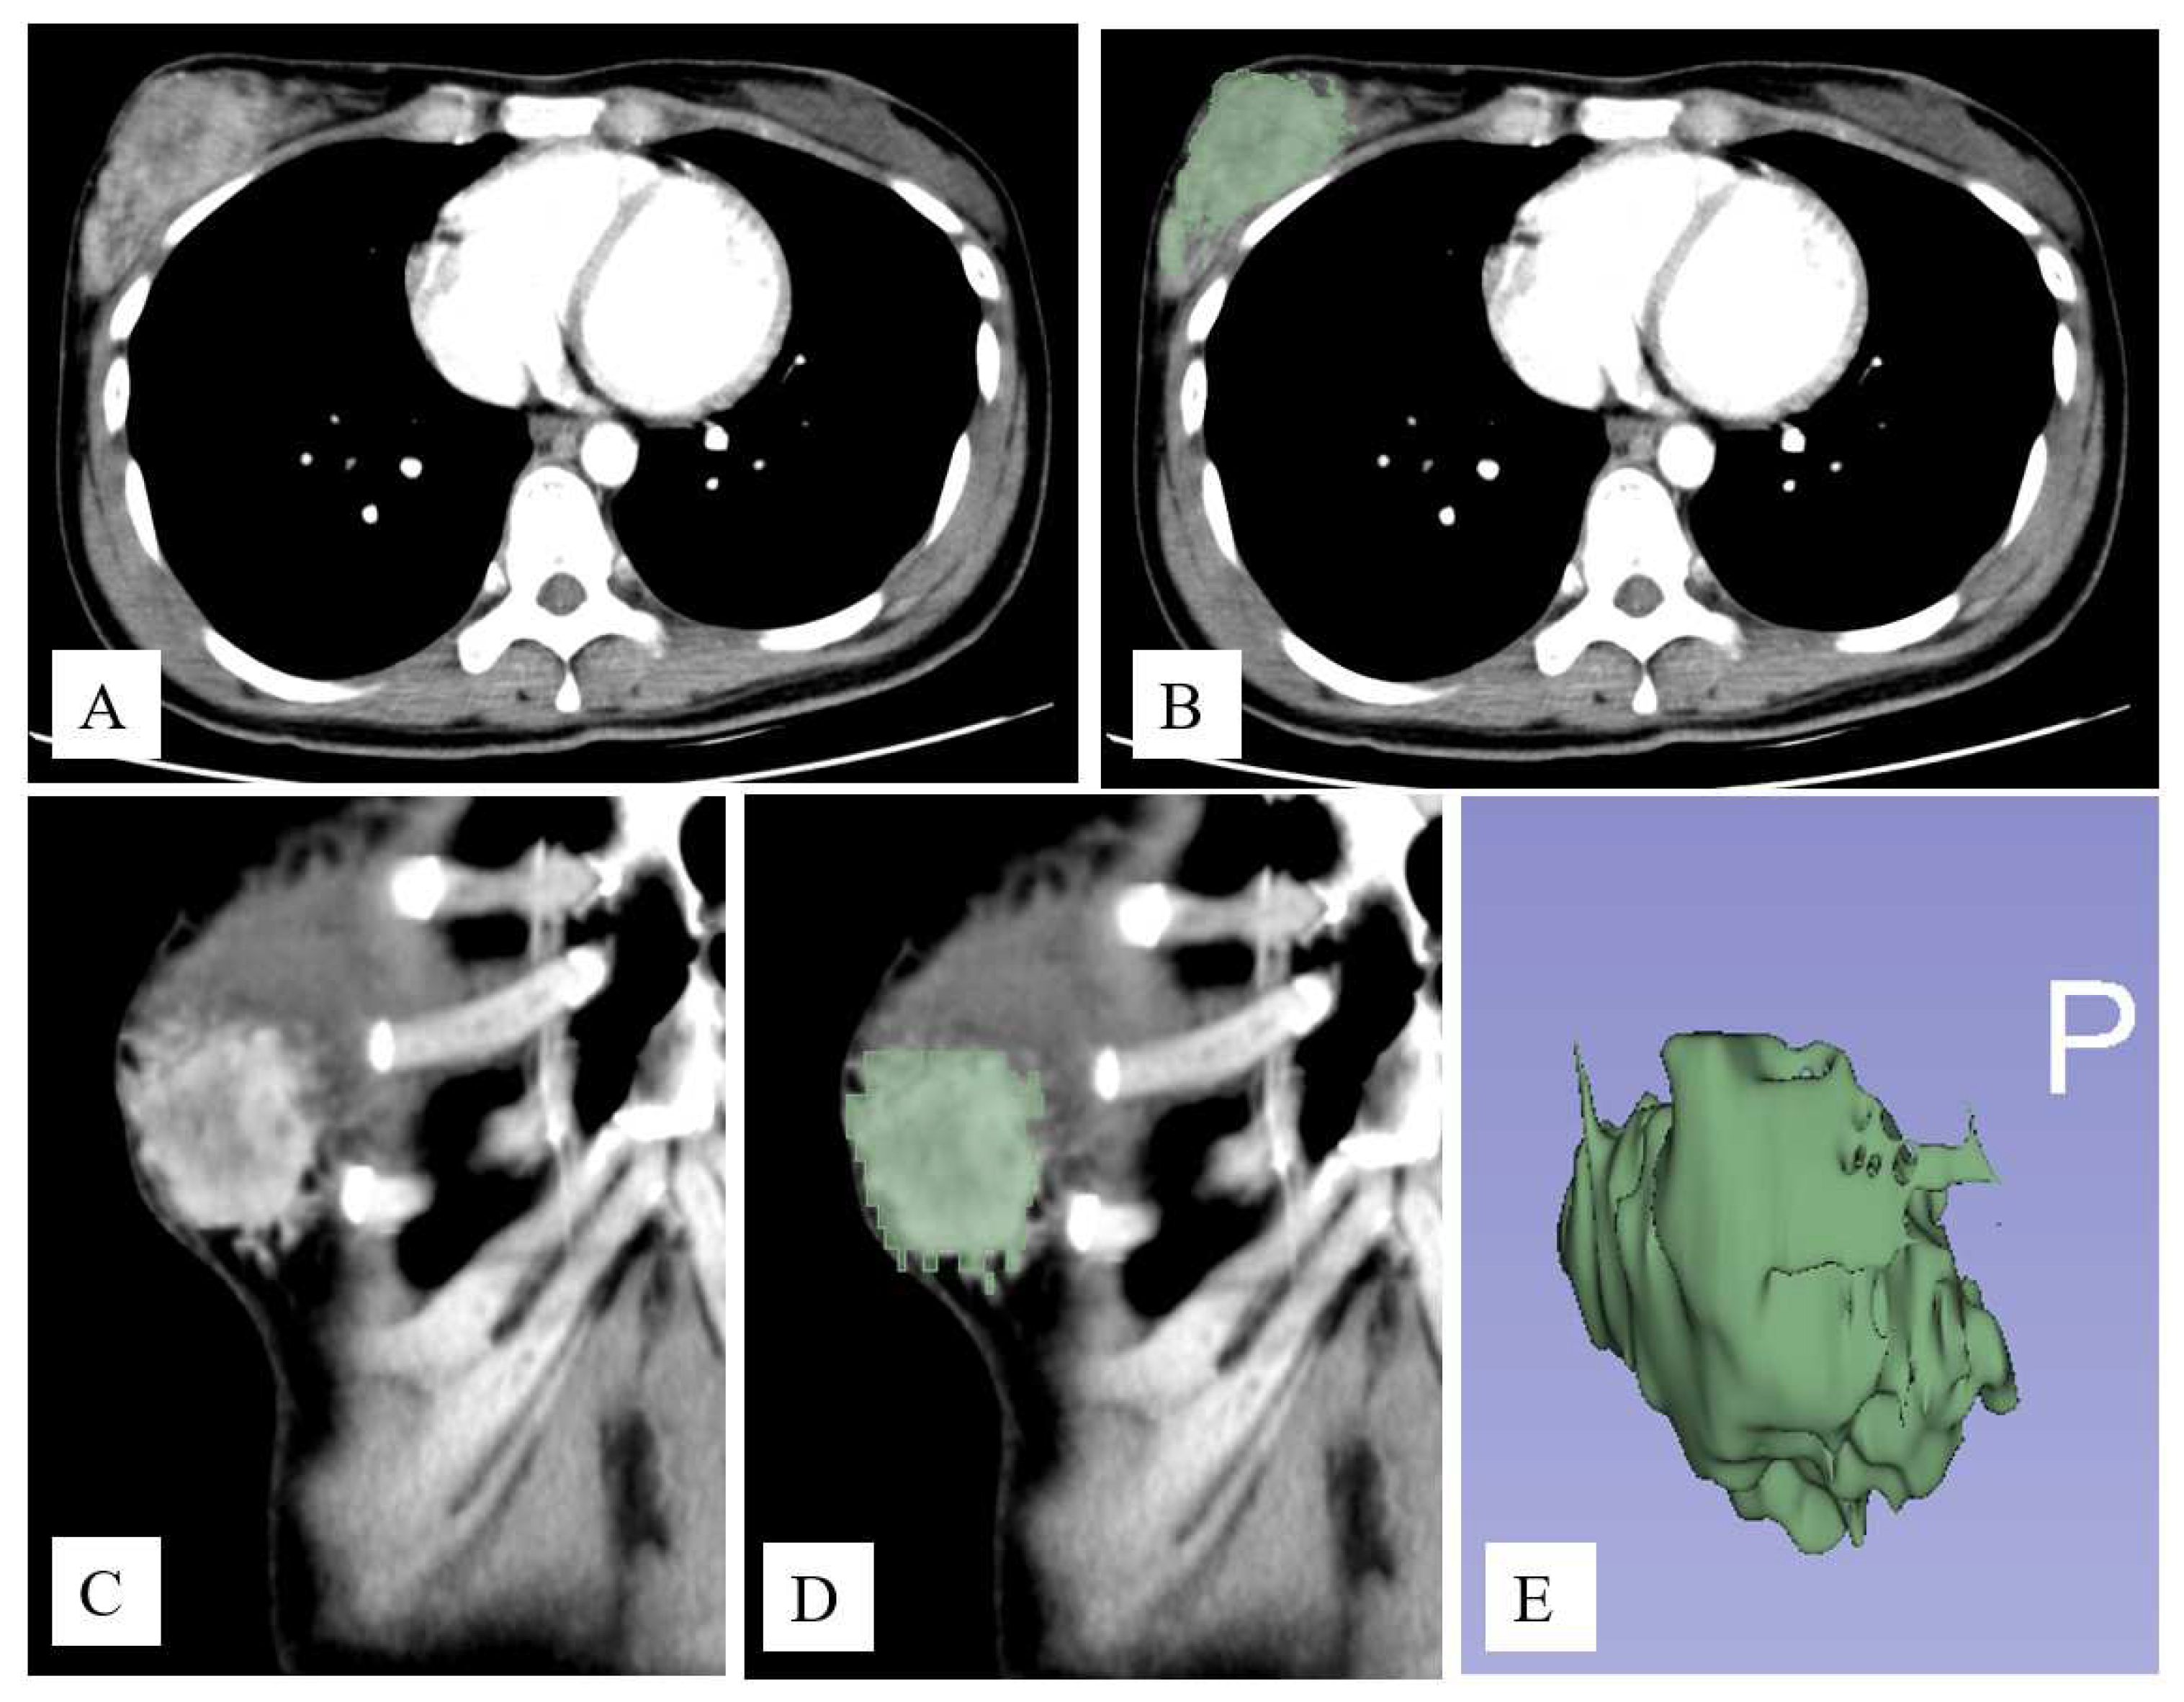

2.4. Image Segmentation and Feature Extraction